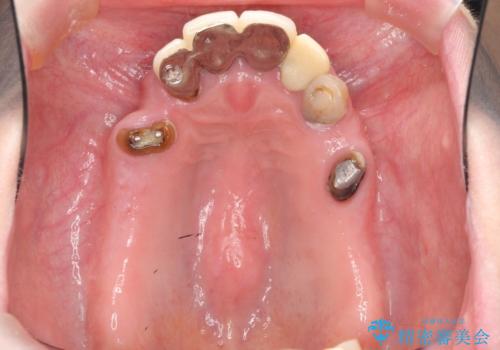

多発した虫歯による咬合崩壊 インプラントを用いた全顎治療

- 「これまで歯の治療をおざなりにしてしまい本当に後悔している。 時間と費用がかかってもいいので、しっかりと安心してかめるような状態にしてほしい。」、と全体的な治療を希望され来院されました。

歯の破折・再発した大きな虫歯・根尖病変・歯の欠損、これらの問題を根管治療・歯周外科・インプラント治療・セラミック補綴を行うことで一つづつ解決し安定した咬合状となるよう治療を進めます。